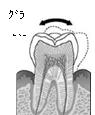

この図をご覧下さい。

歯は歯槽骨という骨に支えられています。

あなたの歯がまだしっかりとしてグラグラともしていないのは、

この歯を支えている骨がしっかりしているからなのです。

歯周病は骨の病気。歯は歯槽骨とう骨に埋まっているのです

骨はつまり基礎です。